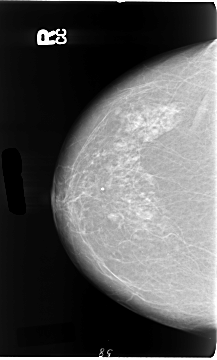

Digital Database for Screening Mammography

Volume: cancer_01 Case: B-3081-1

B_3081_1.RIGHT_CC

B_3081_1.LEFT_CC

DATE_OF_STUDY 18 10 1994

PATIENT_AGE 71

FILM_TYPE REGULAR

DENSITY 2

LEFT_CC LINES 4640 PIXELS_PER_LINE 2768 BITS_PER_PIXEL 12 RESOLUTION 50 OVERLAY

LEFT_MLO LINES 4664 PIXELS_PER_LINE 2784 BITS_PER_PIXEL 12 RESOLUTION 50 OVERLAY